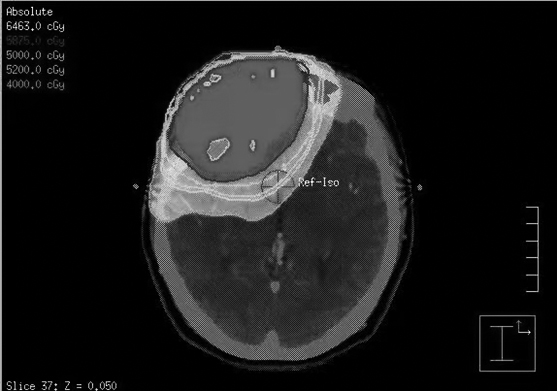

2020年8月,一名38岁、脑瘤术后拟行放疗的女性患者来到河南省人民医院。 患者2020年7月因前额部持续性胀痛伴加重,自行口服止痛药效果欠佳就诊于当地医院。颅脑CT检查结果提示:右额叶占位性病变。医生考虑脑膜瘤,建议进行手术治疗。后来,患者就诊于某三甲医院,进行头颅MRI(磁共振)检查,结果提示:T1呈混杂等低信号,T2呈混杂等高信号,FLAIR(磁共振成像液体衰减反转恢复序列)呈混杂等高信号,DWI(弥散成像序列)呈低、等稍高信号,ADC(表观弥散系数)呈高、等低信号。 为患者注射钆喷酸葡胺后进行扫描,可见明显不均匀强化。MRI检查结果提示:右侧额部占位性病变,考虑脑膜瘤可能性大,孤立性纤维瘤及其他病变不除外。 患者2020年7月31日在河南省人民医院全麻下进行“右额叶肿瘤切除术”。 术后病理检查结果提示:(右额叶)恶性肿瘤,考虑间叶性软骨肉瘤(图1),建议省级专家会诊。免疫检查结果提示:CD56(NK细胞,+),CD99(兔白细胞分化抗原,+),CK(AE1/AE3)(-),Desmin(结蛋白,-),EMA(上皮细胞膜抗原,-),GFAP(神经胶质酸性蛋白,-),Ki67(热点区约30%+),Myogenin(肌细胞生成素,-),Olig-2(+),S-100(-),STAT6(人信号传导转录启动因子6,-),SYN(突触素,-),Vimentin(波形蛋白,-),SMA(平滑肌肌动蛋白,-)。在低倍放大镜下,可见病理切片由大的未分化小细胞、小且圆形或短的梭形细胞和小细胞质组成。细胞核呈圆形或卵形,染色较深,核仁不明显,中间可见少量透明软骨的小岛,软骨分化相对成熟(图1右)。 2020年8月19日,对这个病例,相关专家会诊后报告如下:(右额叶)恶性肿瘤,符合间叶性软骨肉瘤的诊断。 术后,患者的头颅磁共振(3.0T)检查结果提示:与2020年8月27日所拍的片子对比,术区出血灶较前吸收减少;额窦病灶缩小。患者进行了3个周期的化疗。 术后患者间断性头痛,并伴有双侧眼周肿胀。患者进行头颅3.0T磁共振平扫+增强,结果提示:右额叶见斑片状短T1、长T2信号影,FLAIR呈高信号,DWI呈高信号,增强扫描可见局部轻微强化,周边可见水肿带环绕,右侧脑室前角稍受压,中线结构居中。 接诊患者后,我们认为对该患者的诊断有疑点: 1.中枢神经系统缺乏间叶组织,软骨肉瘤的诊断是否成立。 2.术后患者肿瘤占位解除,但患者仍间断性头痛,双侧眼周肿胀,仅用术后改变来解释是否合理?是否存在残余肿瘤? 于是,我们再次阅读患者术前、术后的头颅MRI片,发现患者存在额窦病变,并且在术前、术后MRI影像中未见明显变化。 我们请河南省人民医院健康管理中心的影像专家李永丽会诊。李永丽也认为患者额窦病变与颅内部分影像表现一致,应考虑手术残留病变。但是,软骨肉瘤恶性程度低,对放化疗敏感性低。目前,患者症状明显、残留病灶存在,不同意再次手术,无放疗禁忌证,于2020年9月7日进行放射治疗。 我们给予处方剂量额窦病变PGTV(原发肿瘤计划肿瘤靶区):64Gy(辐射计量单位),PTV1(预防区计划靶区1):60Gy,PTV2(预防区计划靶区2):54Gy(图3),共30次,每周5次;患者在放疗过程中耐受性可,前额疼痛、肿胀症状明显缓解后出院;放疗结束后,多次进行药物治疗。术后1年病情无明显进展。目前,术后放疗和化疗的过程已完成,患者无不适,耐受性尚可,定期复查。患者仍在随访观察中,一般情况好,前额肿胀、疼痛等症状消失,影像检查结果提示:病灶无进展。 软骨肉瘤是骨肿瘤中常见的恶性肿瘤,是由染色体异常引起的软骨组织疾病。迄今为止,颅内软骨肉瘤的起源仍不清楚。颅内间叶性软骨肉瘤是一种罕见的中枢神经系统恶性肿瘤,通常发生于年轻人,约占颅内肿瘤的0.15%。原发性颅内软骨肉瘤绝大多数起源于颅底,预后较差,局部复发的可能性较高。有报道说,与手术结合术后辅助放疗相比,单纯手术似乎是无效的治疗策略。因此,手术结合术后放疗,患者可获得最佳的生存时间。相关研究发现,仅接受手术治疗的软骨肉瘤患者的5年死亡率为26%,而实施术后辅助放疗则使死亡率大幅降低至4%。 近期,许多研究指出,精细的手术切除加上术后放疗,可为这些患者提供最佳的长期预后。相关专家在2002年开展的研究发现,术后放疗可能对这些患者有益。而一项关于此类问题的研究,在2007年也明确指出,放疗是治疗软骨肉瘤的重要辅助疗法。我们为该患者选择术后辅助放疗,使患者1年来保持较高的生活质量,未再出现前额胀痛症状,影像评估稳定。 (作者供职于河南省人民医院)